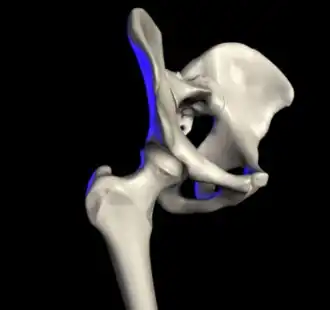

| The hip joint is formed between the femur and acetabulum of the pelvis. | |